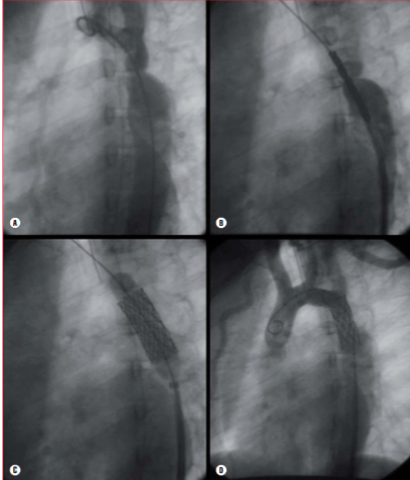

Tecnica per l’impianto di stent

La parte diagnostica è simile alla procedura di angioplastica con palloncino. Dopo aver eseguito l’angiografia in proiezione obliqua anteriore sinistra e laterale, si misurano il diametro del tratto coartato, dell’aorta prossimale e distale all’ostruzione e il tratto che dovrà essere “stentato”. Tutte le misure devono essere eseguite in due proiezioni e poi farne la media. Dopo aver attraversato la coartazione per via retrograda, con un catetere MP, si posiziona una guida Amplatzer extra-stiff con punta “J” nella succlavia destra. Dopo aver rimosso il MP, si porta un long sheath Cook o simili oltre il tratto stenotico. Nei bambini e negli adulti si possono usare gli stent premontati su palloncino, ma la maggior parte dei Centri usa il BIB (balloon in balloon), per prevenire rotture del pallone e dislocazioni dello stent. Il calibro dell’introduttore femorale dipende dallo stent usato. Il palloncino deve essere poco più lungo dello stent, che viene posizionato a cavallo della stenosi. Si eseguono dei test angiografici per verificarne la posizione.

Si gonfia il pallone interno del BIB e, valutata la stabilità e la corretta posizione, si gonfia il palloncino esterno. Si eseguono infine l’angiografia conclusiva e un ritiro per valutarne la pressione arteriosa.